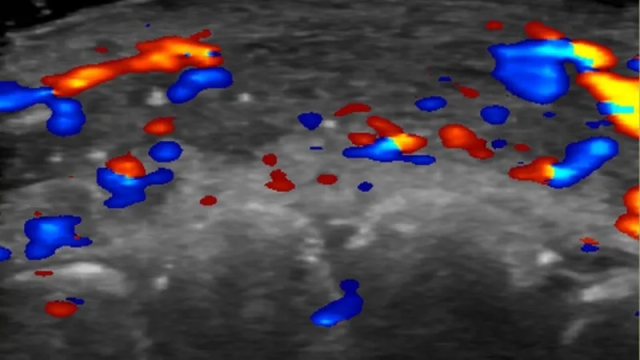

برازیل کی یونیورسٹی آف ساؤ پالو کی ڈاکٹر روزا سگرسٹ کی قیادت میں محققین نے 100 فلر انجیکشن کے کیسز کا الٹراساؤنڈ کے ذریعے مطالعہ کیا جہاں فلرز کے استعمال سے پیچیدگیاں پیدا ہوئی تھیں۔

ڈاکٹر سگرسٹ کا کہنا ہے کہ فلرز دینے سے پہلے الٹراساؤنڈ کے ذریعے خون کی نالیوں کی شناخت ضروری ہے۔

پیچیدگی کی صورت میں الٹراساؤنڈ کی مدد سے صحیح مقام پر علاج کیا جا سکتا ہے۔

غیر ہدایت شدہ انجیکشنز کی بجائے الٹراساؤنڈ سے رہنمائی حاصل کرنے پر کم دوائی استعمال کر کے بہتر نتائج حاصل کیے جا سکتے ہیں۔